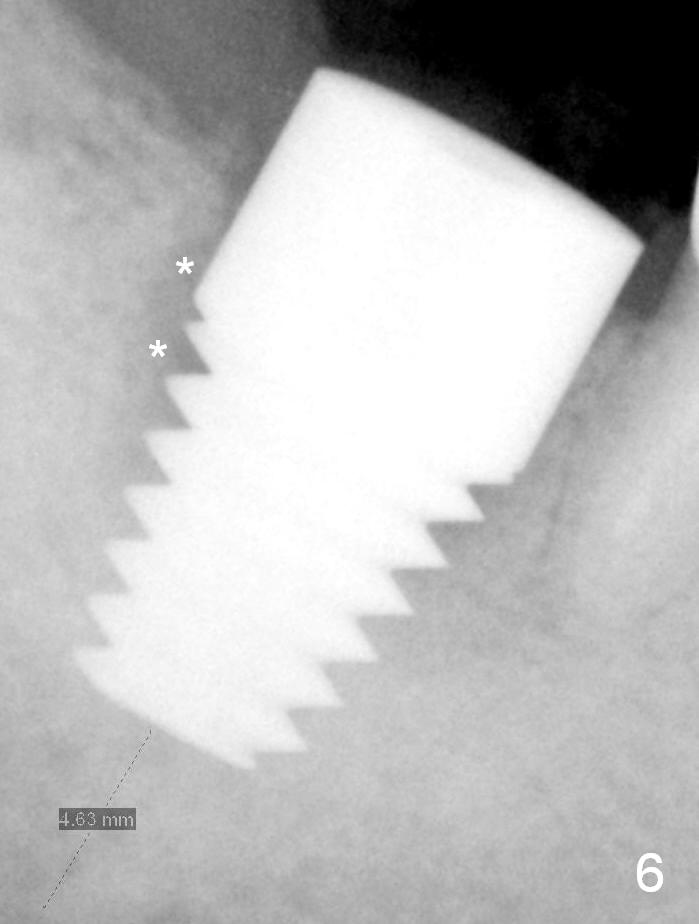

Fig.6 shows a 8x14 mm implant in place with a small gap distally (*). The distal gap has disappeared 5.5 months postop (Fig.13 *). There is no bone loss 26 months post cementation (Fig.14).